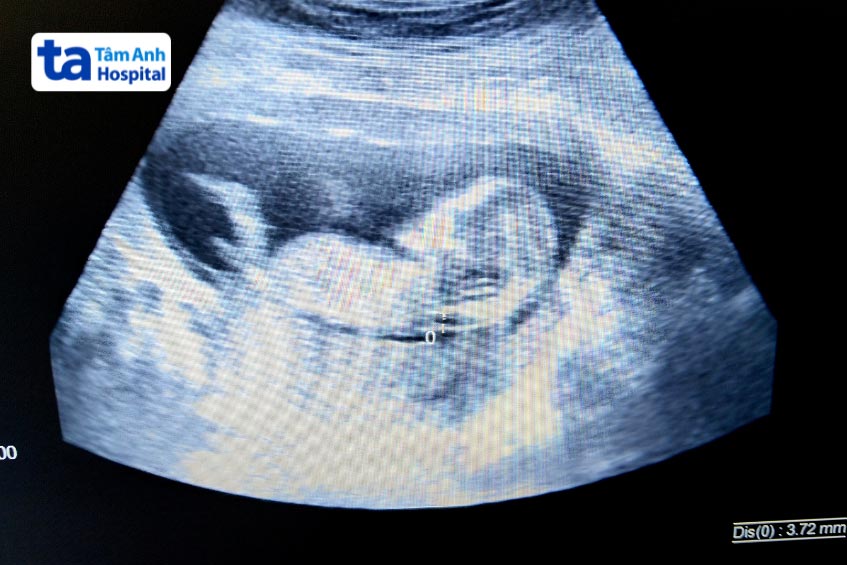

Đo độ mờ da gáy là một phương pháp quan trọng, để đánh giá nguy cơ dị tật thai nhi trong giai đoạn đầu thai kỳ. Phương pháp này được thực hiện từ tuần 11 đến 13 tuần, siêu âm đo độ mờ da gáy sử dụng kỹ thuật siêu âm để đo lượng dịch ở phía sau cổ của thai nhi. Kết quả đo độ dày dịch sau gáy giúp đánh giá nguy cơ mắc hội chứng Down, các tình trạng nhiễm sắc thể dựa trên kết quả đo và các yếu tố khác.

Tại Bệnh viện Đa khoa Tâm Anh, chúng tôi tự hào là địa điểm quy tụ đội ngũ chuyên gia và bác sĩ chuyên môn cao. Cùng với đó, là cơ sở vật chất và hệ thống máy móc hiện đại. Bệnh viện sở hữu các thiết bị siêu âm tiên tiến như siêu âm 3D, 4D, siêu âm Doppler màu thế hệ mới, và máy siêu âm Voluson E10, giúp cung cấp hình ảnh rõ nét và chính xác nhất về sự phát triển của thai nhi.

Dịch vụ sàng lọc trước sinh tại Bệnh viện Đa khoa Tâm Anh không chỉ bao gồm đo độ mờ da gáy mà còn tích hợp các phương pháp xét nghiệm tiên tiến như NIPT để đánh giá nguy cơ bất thường di truyền. Chúng tôi cam kết mang đến dịch vụ chẩn đoán, chăm sóc trong không gian đảm bảo tiêu chuẩn vô trùng, vô khuẩn, nhằm tạo ra sự thoải mái và an tâm tuyệt đối trong mỗi lần thăm khám.